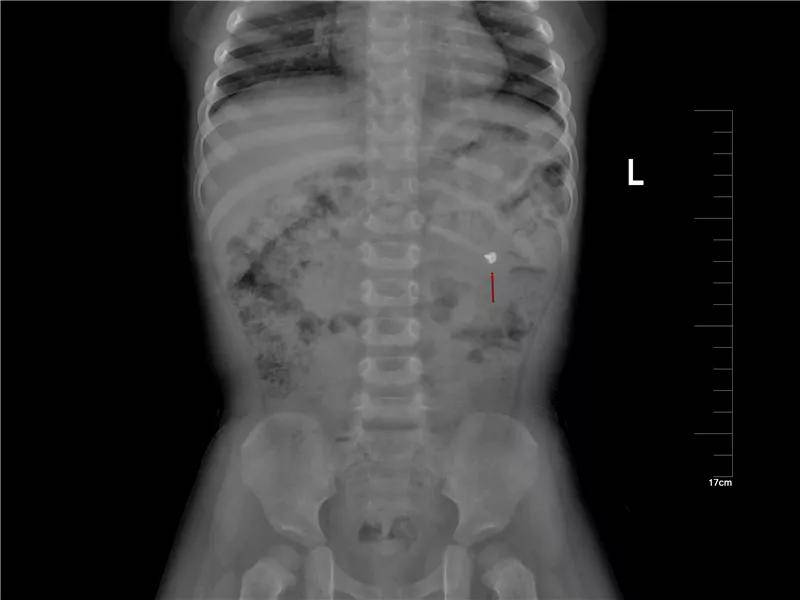

各种年龄误服螺丝钉

这是误服的几个钝头钉,危害相对较小,但看着也很吓人。